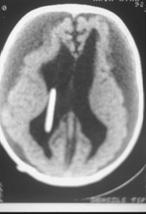

Mekanik sorunlar: Cihazın uygun çalışmasını engelleyen mekanik nedenlerdir. Beyin-omurilik sıvısının içindeki kimyasal maddeler ve beyin dokusu şantı tıkayabilirler. Şanttıkanması olduğunda, kafa içindeki fazla sıvı boşalamayacağı içi tıpkı hidrosefalideki gibi belirtiler görülmeye başlanır. Tıkanma şantın karıncığa takılan bölgesinde, pompa kısmında ya da uç kateter dediğimiz bölümde oluşabilir (Resim 6). Tıkanma nedeni yalnızca doku artıkları ve pıhtılaşmalar değildir; enfeksiyonlara da bağlı tıkanmalar oluşabilir.

Resim 6: (a) BT’de şantın beyin karıncıkları içindeki kateterin tıkanması sonucu yan karıncıkların genişlemesi görülmektedir, (b) yan karıncıktaki kateterin deliklerinin beyin dokusu tarafından tıkandığı görülmektedir.